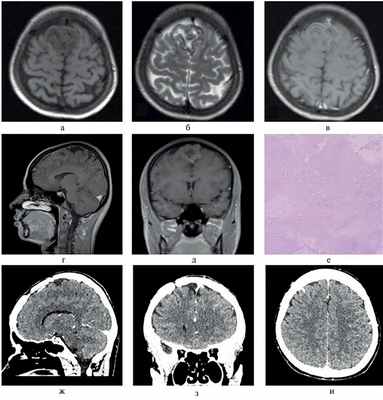

Послеоперационный период протекал гладко, пациентка выписана в удовлетворительном состоянии на 9-е сутки после операции (см. рисунок).

Предоперационные магнитно-резонансные томограммы в T1 (а); T2 (б); T1 с контрастным усилением (в—д). Гистологическая картина микропрепарата (е), окраска гематоксилином и эозином, увеличение ×100. Компьютерные томограммы с контрастным усилением через 6 мес после операции (ж—и).

Результат патологоанатомического исследования биопсийного материала — атипическая хрящевая опухоль/ХС WHO Grade I (ICD-0 code 9220/1).

По данным нейровизуализации можно отметить несколько отличительных признаков ХС. На компьютерных томограммах эти опухоли выглядят изоденсными или иногда гиперденсными с различной гетерогенностью сигнала [5, 6].

Согласно данным литературы, на магнитно-резонансных томограммах эти опухоли чаще всего имеют гипоинтенсивный сигнал на T1 и гиперинтенсивный на T2-взвешенных изображениях с очагами низкого сигнала. Окружающий вазогенный отек, как правило, умеренно выражен. На снимках, выполненных с контрастным усилением, имеется характерная картина отчетливого гетерогенного контрастирования, которое большинство авторов описывают как вид «пчелиных сот» [3, 5, 7, 15, 16, 20—23].

Для ХС характерно наличие очагов кальцификации, видимых при нейровизуализации, однако у ХС большого серповидного отростка они могут быть менее выражены [15]. В соответствии с полученными клиническими и рентгенологическими данными, дифференциальный диагноз ХС проводится со злокачественными менингиомами, гемангиоперицитомами, хондромиксоидными фибромами, метастазами опухолей других органов и АВМ [5, 6]. Мезенхимальные ХС хорошо васкуляризованы и могут потребовать предварительной эмболизации [16].

Несмотря на имеющееся сходство с описанными новообразованиями, ряд конкретных признаков позволяют отличить ХС большого серповидного отростка от других опухолей. В частности, ХС имеют неоднородно интенсивный сигнал на T2-взвешенных изображениях с очагами низкого сигнала в зонах высокой дифференцированности хрящевой ткани (несмотря на отсутствие кальцификации), видимую границу с мягкой мозговой оболочкой, вид «пчелиных сот» и низкую перфузию. Эти признаки отличают ХС от менингиом и гемангиоперицитом. Невыраженный вазогенный отек позволяет отличить их от глиобластом и метастазов, для которых он характерен, а низкая васкуляризация или практически полное ее отсутствие у типичных ХС — от АВМ [5, 19, 21, 23—25].